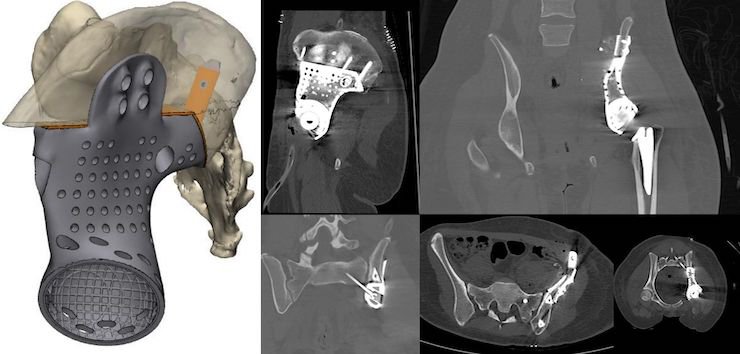

Using this process, MT Ortho has developed a new line of customised cranioplasty prostheses which are now in use throughout Europe and also created solutions for orthopaedic surgery, Oncological orthopaedics, neurosurgery and maxillofacial surgery. In bone cancer treatment, the design freedom enabled by additive manufacturing allows for the development of customised prostheses that consider deformation and the need to adequately distribute loads, while also perfectly reconstructing bone anatomy after demolition surgery is carried out to remove tumours based on the CT imagery.

A close collaboration between surgeon and MT Ortho engineers sees a CT scan of the specific anatomical characteristics of the patient carried out, a conference call held to identify access routes and then the characteristics of the fixing systems be determined with consideration given to the resistance of the material being used. The prosthesis is designed and reviewed by the surgeon, before being printed, along with a backup part, and post-processes with washing and final sterilisation.